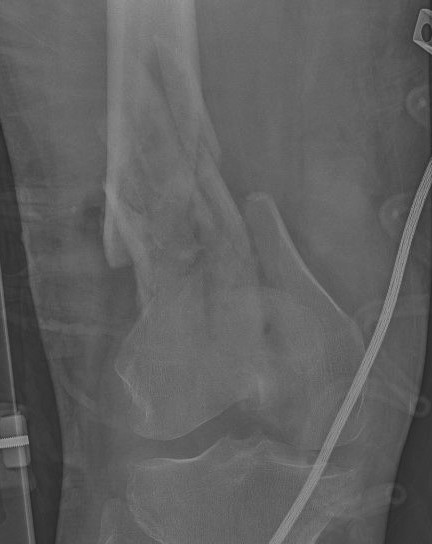

AO Type A: Supracondylar / Extra-condylar

Xray